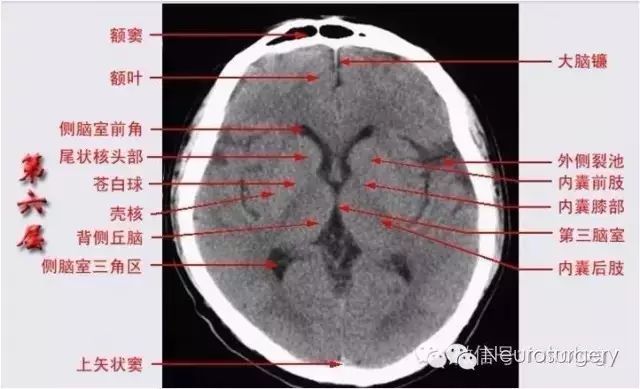

已收藏!颅脑ct解剖口诀 彩色解剖图

额叶 岛叶 苍白球 内囊后肢 第三脑室 壳核 丘脑 胼胝体膝部 尾状核头